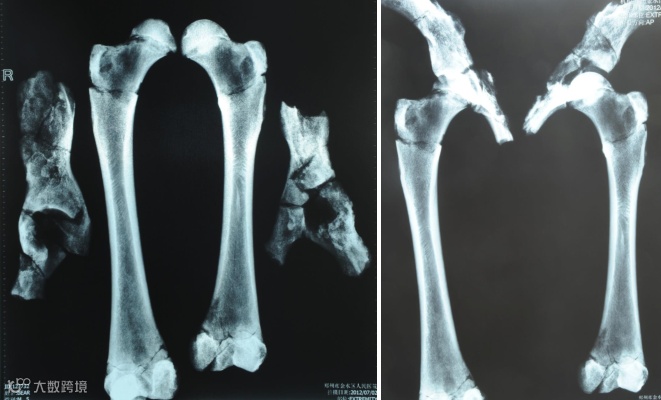

在对这只黑熊进行全面检查时,动物考古工作者发现,黑熊左侧髋骨的臼窝中有明显的赘疣,左侧股骨明显短于右侧股骨,这说明,这只熊在行走时有些坡脚。为了证明这一判断,动物考古工作者对这只黑熊的股骨进行了X射线检查。

河南大学历史文化学院研究生李傲介绍,通过观察X射线扫描的结果,这只黑熊的左侧股骨比右侧股骨要弯曲,并且左侧股骨有很明显的骨折后愈合痕迹,这说明这头黑熊在年幼的时候发生过“青枝骨折”。不过通过对其肱骨等其他四肢骨骼的观察,并没有发现它有严重的营养不良现象。

青枝骨折多见于儿童,“青枝”两个是借用来的,在植物的青嫩枝条中,常常会见到折而不断的情况,因此骨科医生就把这种特殊的骨折称之为“青枝骨折”。